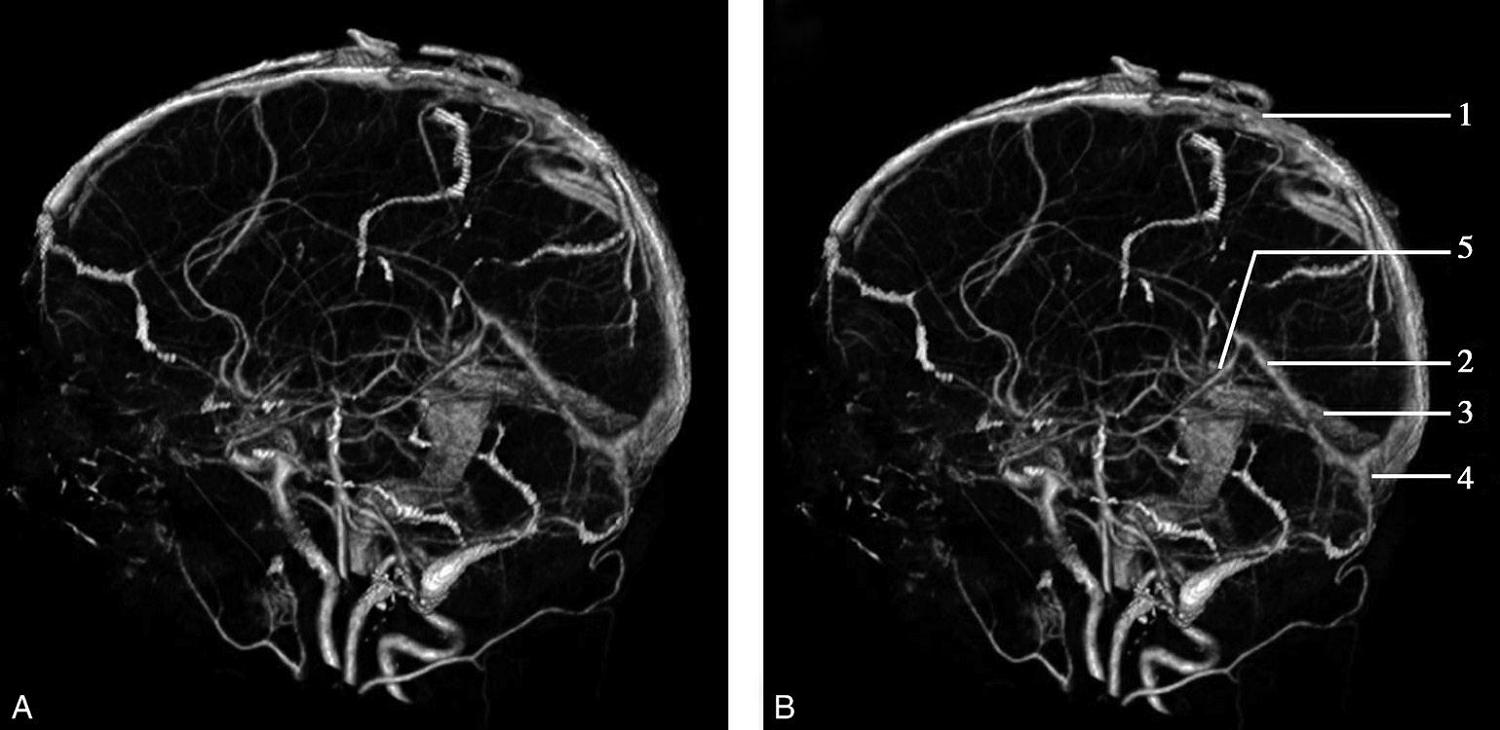

CT血管成像(CT angiography,CTA及CT venography,CTV)通过三维重建技术可显示颅内动静脉的走行、血管壁及血管周围等情况(图1-2-73~图1-2-75)。

图1-2-73 正常颅脑CTA

1.大脑前动脉;2.大脑中动脉;3.颈内动脉;4.大脑后动脉;5.基底动脉;6.椎动脉

图1-2-74 正常椎基底动脉CTA

1.基底动脉;2.颈内动脉;3.颈总动脉;4.颈外动脉;5.椎动脉

图1-2-75 正常颅脑CTV

A.侧位;B.侧位标注

1.上矢状窦;2.直窦;3.乙状窦;4.窦汇;5.大脑大静脉